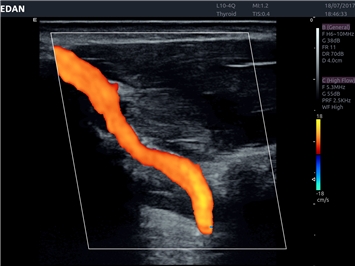

• Сосудистой диагностики

Цветовой допплер:

Да